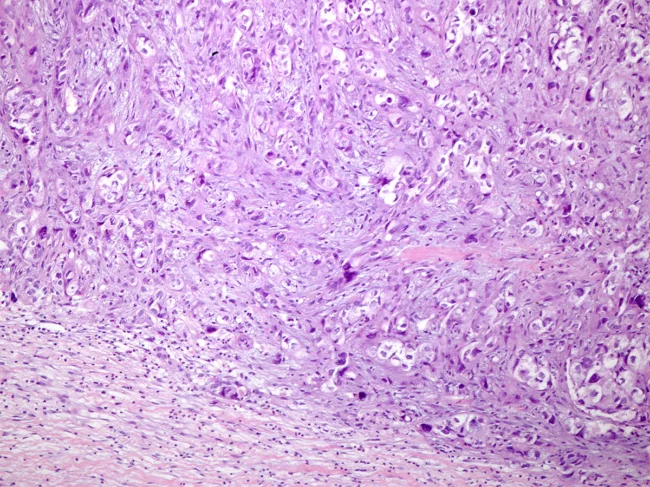

Histology slide of osteosarcoma

Identification of a novel drug and target in osteosarcoma

While current treatments can prolong the life of many patients with the malignant bone cancer osteosarcoma, a substantial proportion have metastasis or recurrence. This highlights the need for more specific, targeted therapies against the disorder, yet the mechanism of pathogenesis is unclear and may be heterogeneous, so no drug targets have been definitively validated. Read More